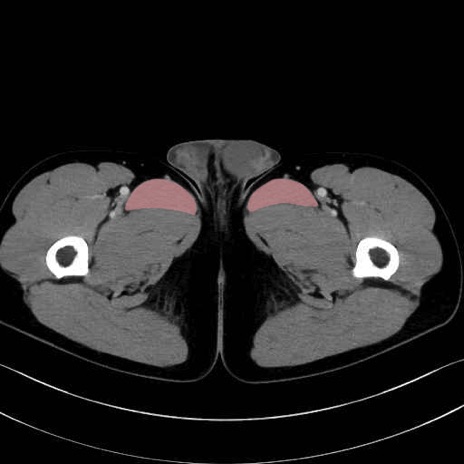

長内転筋(Adductor longus muscle)のCT画像の解剖

6. 大腿内側(内転筋群)

長内転筋 (Adductor longus)